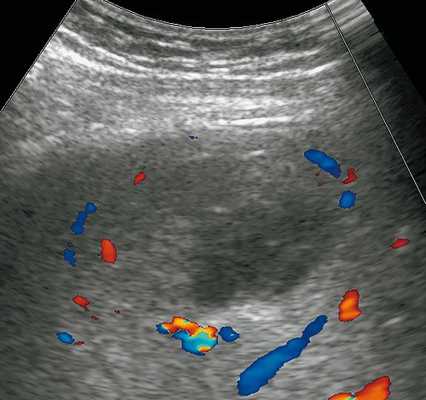

Печень увеличена в размерах: переднезадний размер правой доли 14,3 см (N до 12,5 см), вертикальный размер правой доли 19,0 см (N до 15,0 см), переднезадний размер левой доли 9,3 см (N до 7,0 см). Диафрагмальный край ровный. Структура паренхимы печени неоднородная с наличием в правой доле в проекции V сегмента образования сниженной эхогенности, с несколько нечеткими контурами, размерами до 6,5 х 4,6 х 4,8 см, выраженно неоднородной структуры с наличием в центральных отделах участка умеренно повышенной эхогенности неоднородной структуры размерами 5,8 х 4,8 х 4,2 см, аваскулярного (рис. 1). По периферии образования - деформация сосудистого рисунка (рис. 2). Эхогенность печени обычная. Внутри- и внепеченочные желчные протоки не расширены, стенки их уплотнены. Диаметр воротной вены 1,2 см.

Рис. 2. Режим ЦДК. Описываемое образование аваскулярное. По его периферии - деформация сосудистого рисунка.